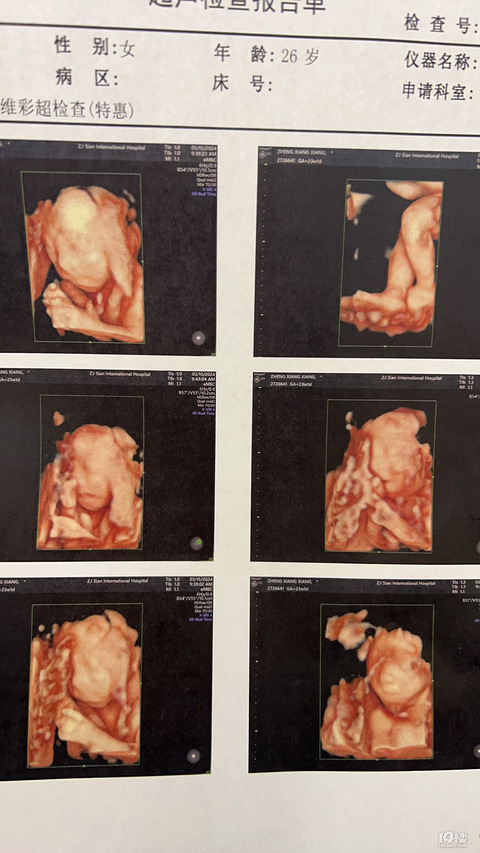

今天孕期21周了,马上可以做4维和孩子见面了,孕反也渐渐结束,打扮的美美的,出去逛街,吃好吃的!希望我的宝宝今天也有一个好心情!